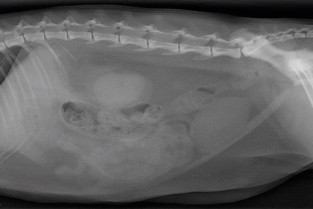

• décrire les principes à respecter pour obtenir une radiographie abdominale de bonne qualité ;

• adopter une méthodologie pour interpréter les affections de la cavité péritonéale et rétropéritonéale chez les carnivores domestiques ;

• décrire l’aspect normal et anormal des organes péritonéaux et rétropéritonéaux chez les carnivores domestiques ;

• détecter une obstruction digestive.

TD de lecture de radiographies numériques

Travaux dirigés

Correction collégiale, discussion